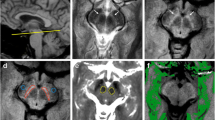

The adult LC and SN are unusual in that they are populated by large (up to 40 μm diameter; Fig. 1a) noradrenergic (NA) and dopaminergic (DA) neurons, which contain numerous organelles that can take up to 50% of the cell volume (Halliday et al. 2005) and are filled with NM macromolecules (Fig. 1b). NM is a large (~ 30 nm) polymer that is a by-product of noradrenaline (NE)/dopamine (DE) synthesis (Zecca et al. 2004; Zucca et al. 2006). The source of the LC and SN MRI contrast has been suggested to relate to this high concentration of NM (Cassidy et al. 2019), based on the observation that the reduced MT effect is specifically observed in the LC and SN, the centers of NE and DA synthesis in the brain (Keren et al. 2009). Furthermore, histology studies showed a positive correlation between MT signal and the number of NM neurons or NM in the SN (Cassidy et al. 2019; Kitao et al. 2013), as well as spatial overlap between TSE hyperintensities and NM accumulation in the LC (Keren et al. 2015). The precise reason for this relationship between NM accumulation and reduced MT effects is, however, unclear. NM macromolecules are reported to be slightly paramagnetic and also tend to bind metals, which may shorten the T1 of the free water (Ju et al. 2013; Lee et al. 2016; Trujillo et al. 2016), thus potentially decreasing the longitudinal magnetization of both the free and bound water pools compared to adjacent brain matter (Fig. 1e). We should note though that the only NM model MRI study the authors are aware of, showed that NM on its own does not significantly affect MT behavior (Trujillo et al. 2016). Alternatively, it has been hypothesized that NM macromolecules may preferentially shorten the T1 of the bound pool (Langley et al. 2015), which would reduce the available magnetization for exchange (Fig. 1f). It is furthermore possible that the reduced MT saturation relates to a smaller macromolecular fraction, due to a lower concentration of lipids such as myelin on the cell’s axons, in line with the typical MT contrast observed between gray matter (GM) and white matter (WM). This may be further enhanced by the large cell size of noradrenergic neurons (up to 40 μm (Kimberly Simpson 2007)), which may result in a smaller bound-to-free water ratio (Fig. 1g). Finally, it was recently put forward that the large cell diameter of NA and DA neurons may produce a large intra-cellular free water proton pool which may show a short T1 due to a high concentration of paramagnetic ions, such as from Copper (Cu) within the cell body (Fig. 1h) (Watanabe et al. 2019). The last 2 hypotheses were further supported by a recent publication that showed smaller pool size ratio (Trujillo et al. 2019).

a–b, Photomicrography of human LC (modified with permission from (Kimberly Simpson, 2007)). a Tyrosine hydroxylase was used to visualize noradrenergic (NA) cells (white arrows). NA cells show a remarkably big diameter, up to 30–40 μm. b Melanin accumulation (black arrows) largely overlaps with the NA cells as shown in a. c–d, Axial slice of human brainstem at the level of LC (modified with permission from (Priovoulos et al. 2018)). c TSE with short TE is typically used to visualize the LC as hyperintense. d MT image of the same participant. A similar hyperintensity appears, indicating that the TSE is related to implicit MT. TSE/MT signal in LC and SN has been shown to spatially overlap with the NA (Keren et al. 2015) and dopaminergic (DA) neurons respectively (Kitao et al. 2013). e–h, Hypotheses for LC and SN MRI contrast following off-resonance saturation. The black arrows indicate the transfer of magnetization from the bound pool to the free water pool. e The presence of the NM and metals, for example iron bound to ferritin (Fe), may shorten the free water T1 so that the pool recovers faster from on- and off-resonance saturations and the LC and SN appear hyperintense. f The proximity of NM and NM-bound metals to the lipids of the membrane (LB) may shorten the T1 of the bound pool. g The LC and SN, as gray matter regions, may show a lower macromolecular content fraction due to less myelination (LB) and/or a large cellular body. h The unusually large NA and DA cells may result in a big pool of intra-cellular water protons. The presence of ions such as copper (Cu) within the NA neurons may shorten the T1 of the intra-cellular water pool causing the LC and SN to appear hyperintense